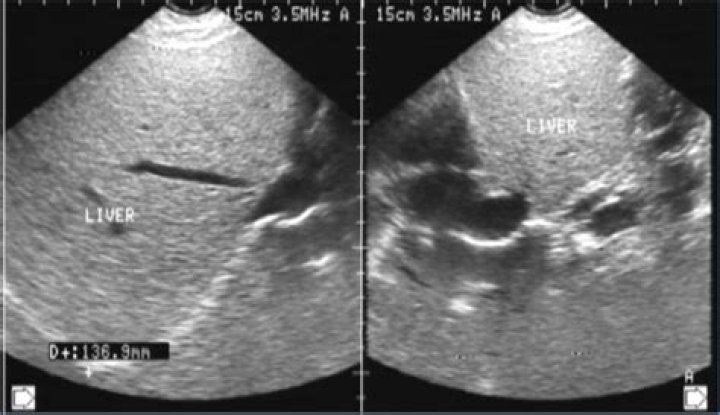

Definition. The appearance of the liver in sonographic images is normally uniform. This term applies when there is an irregular or non-uniform appearance of the liver parenchyma in liver sonography. [ from HPO]

Does fatty liver cause coarse Echotexture?

An ultrasound examination is usually reported as showing a bright or fatty liver. In those with cirrhosis a heterogeneous or coarse echotexture, a nodular outline or splenomegaly may be found, but patients with cirrhosis may have a normal ultrasound.